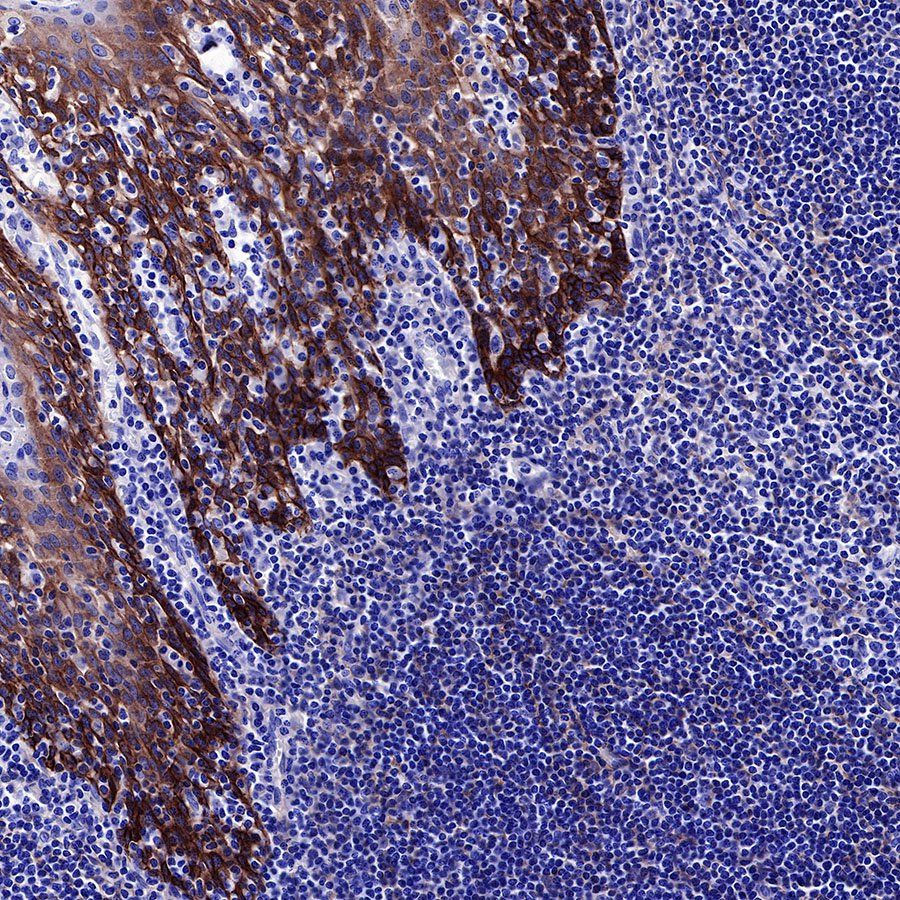

IHC shows positive staining in paraffin-embedded human tonsil. Anti-EGFR antibody was used at 1/2000 dilution, followed by a HRP Polymer for Mouse & Rabbit IgG (ready to use). Counterstained with hematoxylin. Heat mediated antigen retrieval with Tris/EDTA buffer pH9.0 was performed before commencing with IHC staining protocol.

IHC shows positive staining in paraffin-embedded human endometrial cancer. Anti-EGFR antibody was used at 1/2000 dilution, followed by a HRP Polymer for Mouse & Rabbit IgG (ready to use). Counterstained with hematoxylin. Heat mediated antigen retrieval with Tris/EDTA buffer pH9.0 was performed before commencing with IHC staining protocol.

IHC shows positive staining in paraffin-embedded human cervical squamous cell carcinoma. Anti-EGFR antibody was used at 1/2000 dilution, followed by a HRP Polymer for Mouse & Rabbit IgG (ready to use). Counterstained with hematoxylin. Heat mediated antigen retrieval with Tris/EDTA buffer pH9.0 was performed before commencing with IHC staining protocol.

IHC shows positive staining in paraffin-embedded human lung squamous cell carcinoma. Anti-EGFR antibody was used at 1/2000 dilution, followed by a HRP Polymer for Mouse & Rabbit IgG (ready to use). Counterstained with hematoxylin. Heat mediated antigen retrieval with Tris/EDTA buffer pH9.0 was performed before commencing with IHC staining protocol.